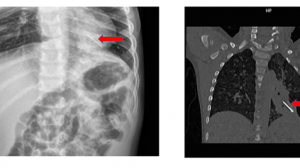

Vừa qua Bệnh viện Nhi Đồng Thành Phố tiếp nhận một trường hợp trẻ S. T. T. N. 15 tháng, nữ, ngụ ở Sóc Trăng. Khai thác bệnh sử: trước nhập viện một ngày trẻ chơi một mình ở sàn nhà,có các hạt hướng dương, hạt mãng cầu, hột nhãn thì người nhà phát hiện trẻ tím tái kèm ho sặc sụa, nên đưa trẻ đến bệnh viện huyện sơ cứu rồi chuyển lên bệnh viện tỉnh, đặt nội khí quản giúp thở, chuyển Nhi đồng cần Thơ trong tình trạng tím tái, SpO2 60%, HA 61/35mmHg, Xquang tràn khí màng phổi trái, xẹp toàn bộ phổi phải, xử trí đặt dẫn lưu màng phổi trái, kháng sinh vancomycin, imipenem, vận mạch: adrenalin, noradrenalin, dobutamin, chuyển Bệnh viện Nhi Đồng Thành Phố.

Tại đây, ghi nhận trẻ mê, tím tái / thở máy, SpO2 50%, mạch quay bắt rõ 170 l/phút, tim đều rõ 170 l/phút, không âm thổi, phế âm phổi trái nghe nhỏ, phế âm phổi phải không nghe, tràn khí dưới da. Bụng mềm, gan không to. Chẩn đoán dị vật đường thở, biến chứng tràn khí màng phổi trái. Xử trí: giúp thở, vận mạch, kháng sinh, hội chẩn ê kíp nội soi hô hấp tiến hành gây mê, dùng ống soi mềm soi qua ngã miệng, ghi nhận hạ họng và thanh quản thông thoáng, 2 dây thanh khép mở tốt. Gây tê 2 dây thanh với Lidocain 2%, ống soi đi tiếp. Khí quản thông thoáng, không dị vật, ghi nhận phế quản gốc phải có khối dị vật màu nâu, xung quang có đọng đàm trắng đục, bít hoàn toàn phế quản gốc phải. Gây tê phế quản gốc P với Lidocain 2%, dùng kiềm răng chuột gắp và kéo dị vật 2 lần đến hạ thanh môn bị vướng, dị vật rớt xuống lại carina. Tiếp tục dùng kiềm răng chuột kéo lần thứ 3 thành công, dị vật là hạt mãng cầu. Soi kiểm tra thấy phế quản gốc P thông thoáng, đọng đàm đục ở phế quản thùy giữa, bơm rửa và hút sạch đàm quan sát không còn dị vật. Phế quản thùy trên phải thông thoáng. Phế quản gốc trái và phế quản phân thùy bên trái thông thoáng. Sau thủ thuật SpO2 BN đạt 93%, mạch 140 l/ph, thông khí phổi phải tốt. Tuy nhiên sau nội trẻ vẫn còn viêm phổi, suy hô hấp, sốt cao, tri giác lơ mơ mê, huyết áp tụt, được tiếp tục giúp thở, kháng sinh phổ rộng, vận mạch, hạ sốt, truyền máu. Kết quả sau một tuần điều trị tình trạng trẻ cải thiện dần, ngưng được vận mạch, cai được máy thở, tỉnh táo tiếp xúc tốt.